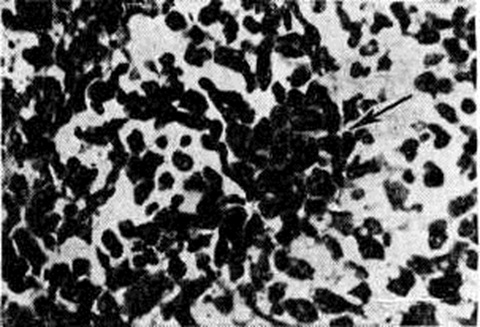

Рис. 6.

Дрожжеподобные клетки грибка, захваченные макрофагами (указано стрелкой). Окраска азур-эозином.